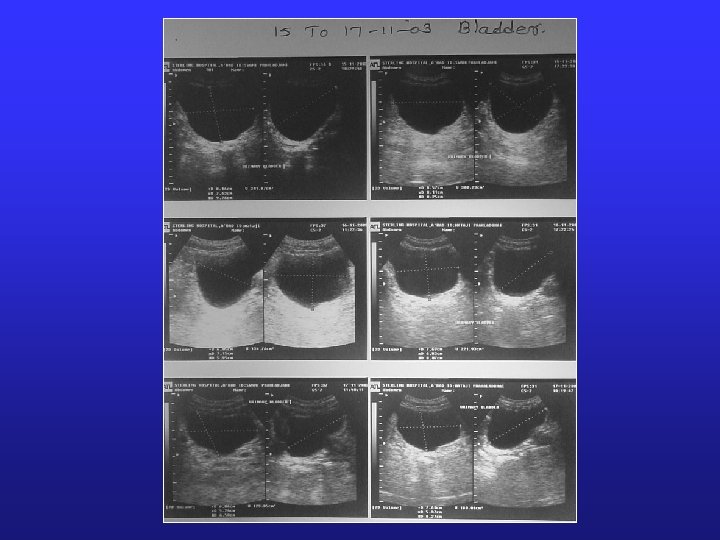

§ After day 10, the committee declared that it is satisfied with following matter: § The protocol was strictly adhered to. § Mr. Jani has not passed or dribbled urine during these 10 days. § He has not taken anything by mouth or by any other route not even water for 10 days. § All his parameters are till date within physiological range. § He has shown evidence of formation of urine, which seems to be reabsorbed from his bladder wall. However at present the committee does not have any scientific explanation for the same but the help of senior scientists and medical personnel of the country is being taken for the same.

Daily Checking § General clinical examination § Daily weight (Varied from 42 kg to 38 kg) § Vital data like Temperature, Pulse, BP and Respiration. § Pulse: 42 -46/min § RR: 12 -16 min § BP: 110/60 mm. Hg § (Vitals s/o some autonomic control ? ) § Bladder capacity was checked by ultrasound twice daily

USG Bladder

13/11/2003 14/11/2003 15/11/2003

18/11/2003